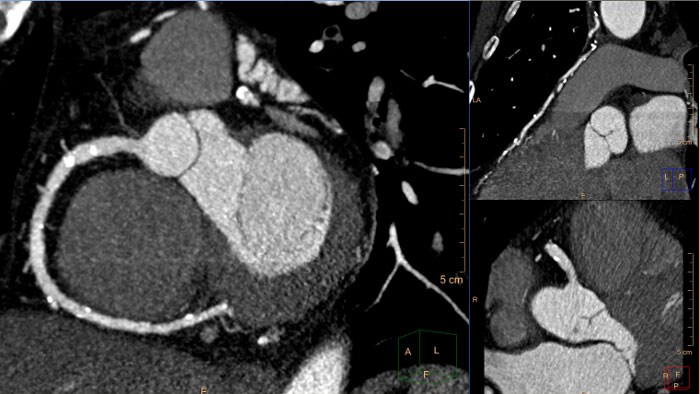

Mejore su experiencia de interpretación de RM cardíaca

La suite de RM cardíaca estrena una nueva apariencia galardonada³, que permite una revisión y análisis sin interrupciones de estudios de RM cardíaca en un entorno completo. Experiencia de lectura mejorada con visualización multimodal en 2D y 3D, comparación con versiones anteriores y diseños flexibles y personalizados. Entorno muy intuitivo que permite a los usuarios completar la mayoría de las tareas con una formación mínima⁴.